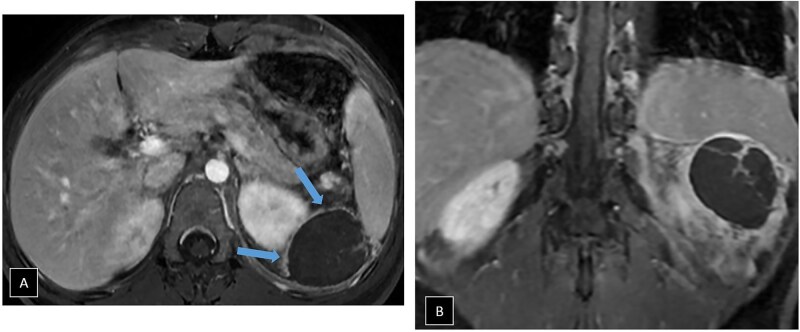

Accessory spleen torsion is a rare but important cause of acute abdominal pain, often presenting with non-specific symptoms that overlap with more common abdominal pathologies. This case report discusses a 19-year-old female who presented with left-sided flank pain and leucocytosis. Imaging with abdominal CT and MRI revealed a well-defined lesion near the spleen and kidney, with mild vascular engorgement and surrounding inflammation. While these findings raised suspicion for accessory spleen torsion, the diagnosis was not immediately clear. The lesion's location, vascular congestion, and absence of typical characteristics for other pathologies, such as haematomas, abscesses, mesothelial cysts, or lymphangiomas pointed towards torsion, but confirmation required surgical intervention. During laparoscopic exploration, a 5 cm accessory spleen with ischaemic changes due to torsion of its pedicle was identified and successfully removed without complications. Accessory spleens, present in 10%-30% of the population, are usually asymptomatic but can become problematic if torsion, rupture, or infarction occurs. Imaging plays a critical role in identifying torsion, with CT and MRI revealing the characteristic "whirlpool sign" and vascular congestion. Early recognition is crucial to prevent complications such as necrosis and rupture, and surgical intervention, typically laparoscopic splenectomy, is the treatment of choice. This case highlights the importance of considering accessory spleen torsion in the differential diagnosis of acute abdominal pain, particularly in young patients with non-specific symptoms. Awareness of this condition can improve early diagnosis and outcomes, preventing severe consequences.

Abstract Image